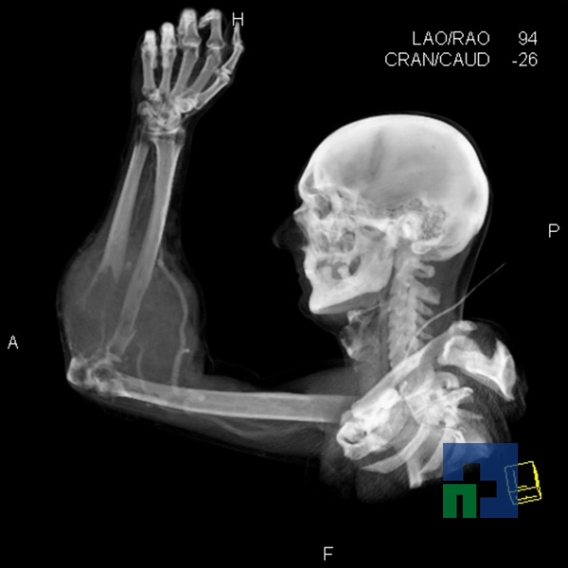

În cazul traumatismelor cranio-cerebrale:

- Diagnosticul traumatismelor de bază de craniu

- Diagnosticul fracturilor:

- Unice

- Multiple

- Cu înfundare

- Complexe cranio-sinusale

- Complexe cranio-etmoidale

- Complexe cranio-orbitare

- Complexe cranio-faciale